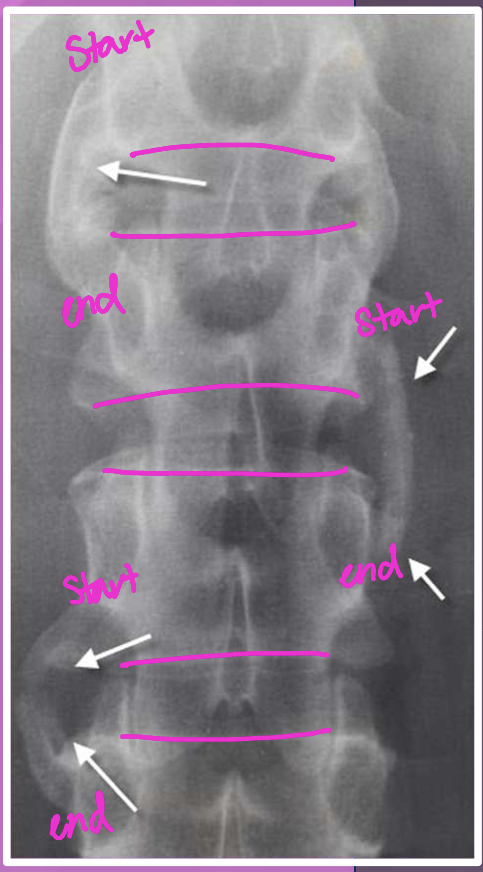

What two findings of AS are found in this image

Corner erosions (Romanus lesions)

Reactive sclerosis (shiny corner)

Loss of anterior concavity (vertebrae squaring)

Where should you be looking every time you think the disease could be AS

SI joints